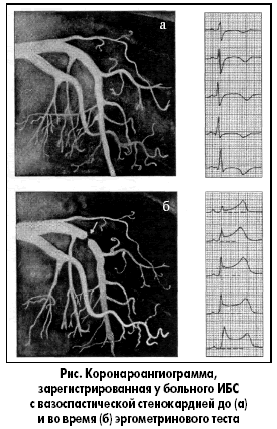

Коронарная ангиография

К сожалению, зафиксировать коронароспазм при спонтанной вариантной стенокардии довольно сложно. Вследствие этого целесообразно применение функциональных проб для провокации спазма коронарных артерий.

Во многих коронарографических центрах применяют ацетилхолиновую инъекцию в коронарные артерии и внутрикоронарную пробу с эргометрином. Данные методы считаются золотым стандартом в диагностике вариантной стенокардии.

Следует отметить, что внутривенную эргометриновую пробу, которую регистрируют с помощью ЭКГ или сцинтиграфии, по уровню чувствительности и специфичности считают наиболее адекватной для выявления вазоспастических реакций у больных ИБС. Ацетилхолиновый и эргометриновый тесты – безопасны при условии, если препарат избирательно вводится в каждую из трех крупных коронарных артерий. Провокационные тесты без коронарной ангиографии или у пациентов с окклюзией коронарных артерий высокой степени проводить не рекомендуется.

После введения эргометрина наблюдается выраженный спазм проксимальной части передней межжелудочковой ветви (ПМЖВ) левой коронарной артерии – динамическая окклюзия (рис.).